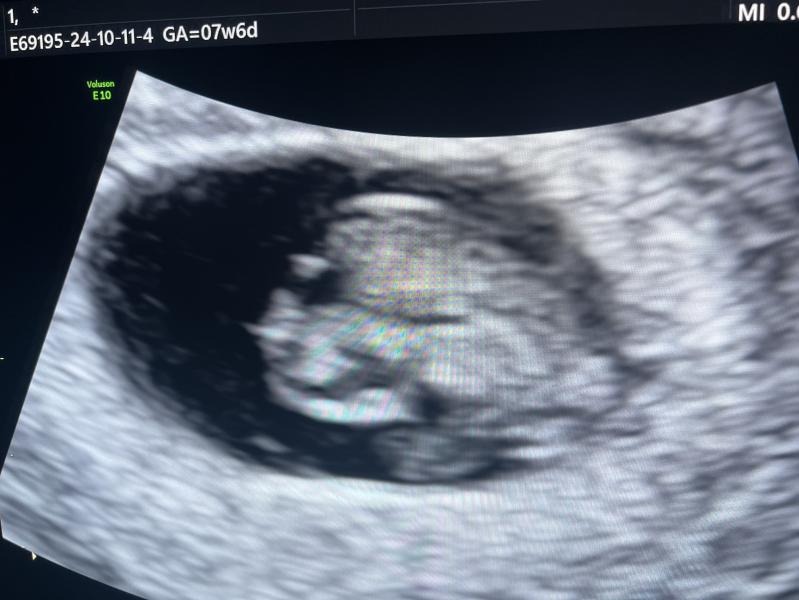

На узи на 8 недели в заключении написали :,, Обращает на себя внимание голова эмбриона и мозговые пузыри ‘’. Что с этим делать ? У кого-нибудь было что-нибудь подобное ?

Прикрепила фото узи и заключение